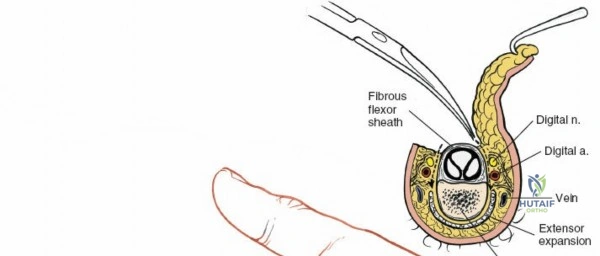

A thorough understanding of the intricate anatomy and biomechanics of the flexor tendon system is non-negotiable for any surgeon employing a volar approach. The digital flexor system comprises the Flexor Digitorum Superficialis (FDS) and Flexor Digitorum Profundus (FDP) tendons. The FDP tendon originates from the ulna and interosseous membrane, inserting onto the volar base of the distal phalanx, primarily responsible for DIP joint flexion. The FDS tendon originates from the medial epicondyle, ulna, and radius, typically bifurcating around the FDP in the region of the proximal phalanx (Camper's chiasm) before inserting onto the middle phalanx, primarily flexing the PIP joint.

Within the fibro-osseous tunnel, these tendons are enveloped by a synovial sheath that facilitates smooth gliding and nutrition. The integrity of the pulley system, composed of annular (A) and cruciate (C) ligaments, is critical for preventing tendon bowstringing and maintaining efficient mechanical advantage. Typically, five annular pulleys (A1-A5) and three cruciate pulleys (C1-C3) are described in each finger. The A1 pulley is at the metacarpophalangeal (MCP) joint level, A2 at the proximal phalanx, A3 at the proximal interphalangeal (PIP) joint, A4 at the middle phalanx, and A5 at the distal interphalangeal (DIP) joint. The A2 and A4 pulleys are considered the most critical for preventing significant bowstringing.

The digital neurovascular bundles (NVBs) run along the radial and ulnar sides of each digit, volar to the collateral ligaments, providing sensation and vascularity. Proper identification and protection of these bundles are paramount during any volar dissection. Proximally, the median nerve gives rise to recurrent motor branches to the thenar muscles and sensory branches to the thumb, index, middle, and radial half of the ring finger. The ulnar nerve supplies the hypothenar muscles, adductor pollicis, and interossei, along with sensory innervation to the little finger and ulnar half of the ring finger. The palmar arches (superficial and deep) provide critical vascular supply to the hand.

After marking the incision, the skin and subcutaneous tissues are carefully incised. In the digits, the triangular skin flaps created by the Bruner incision are elevated using fine skin hooks or small self-retaining retractors. Dissection should proceed in the subcutaneous plane, superficial to the digital neurovascular bundles, which run along the radial and ulnar borders of the digit, immediately adjacent to the flexor sheath.

Care must be taken to identify and protect these bundles. Any existing lacerations or hematomas are debrided. The digital nerves and vessels are carefully dissected free from the surrounding connective tissue and retracted, typically dorsally and laterally, using vessel loops or fine retractors to provide clear access to the underlying flexor sheath.

Fibrous Flexor Sheath Exposure

Once the subcutaneous tissue and neurovascular bundles are retracted, the fibrous flexor sheath is visible. This appears as a glistening white, tough structure enveloping the flexor tendons.